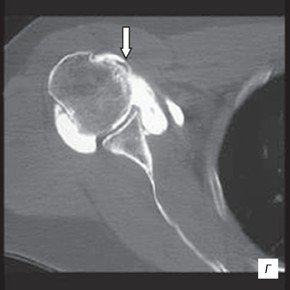

в) Подвывих сухожилия двуглавой мышцы (головка стрелки) без повреждения поперечной связки (стрелка).

г) На компьютерной артрограмме плеча того же пациента отмечается подвывих сухожилия двуглавой мышцы (стрелка) в проксимальном направлении с пустым межбугорковым углублением.